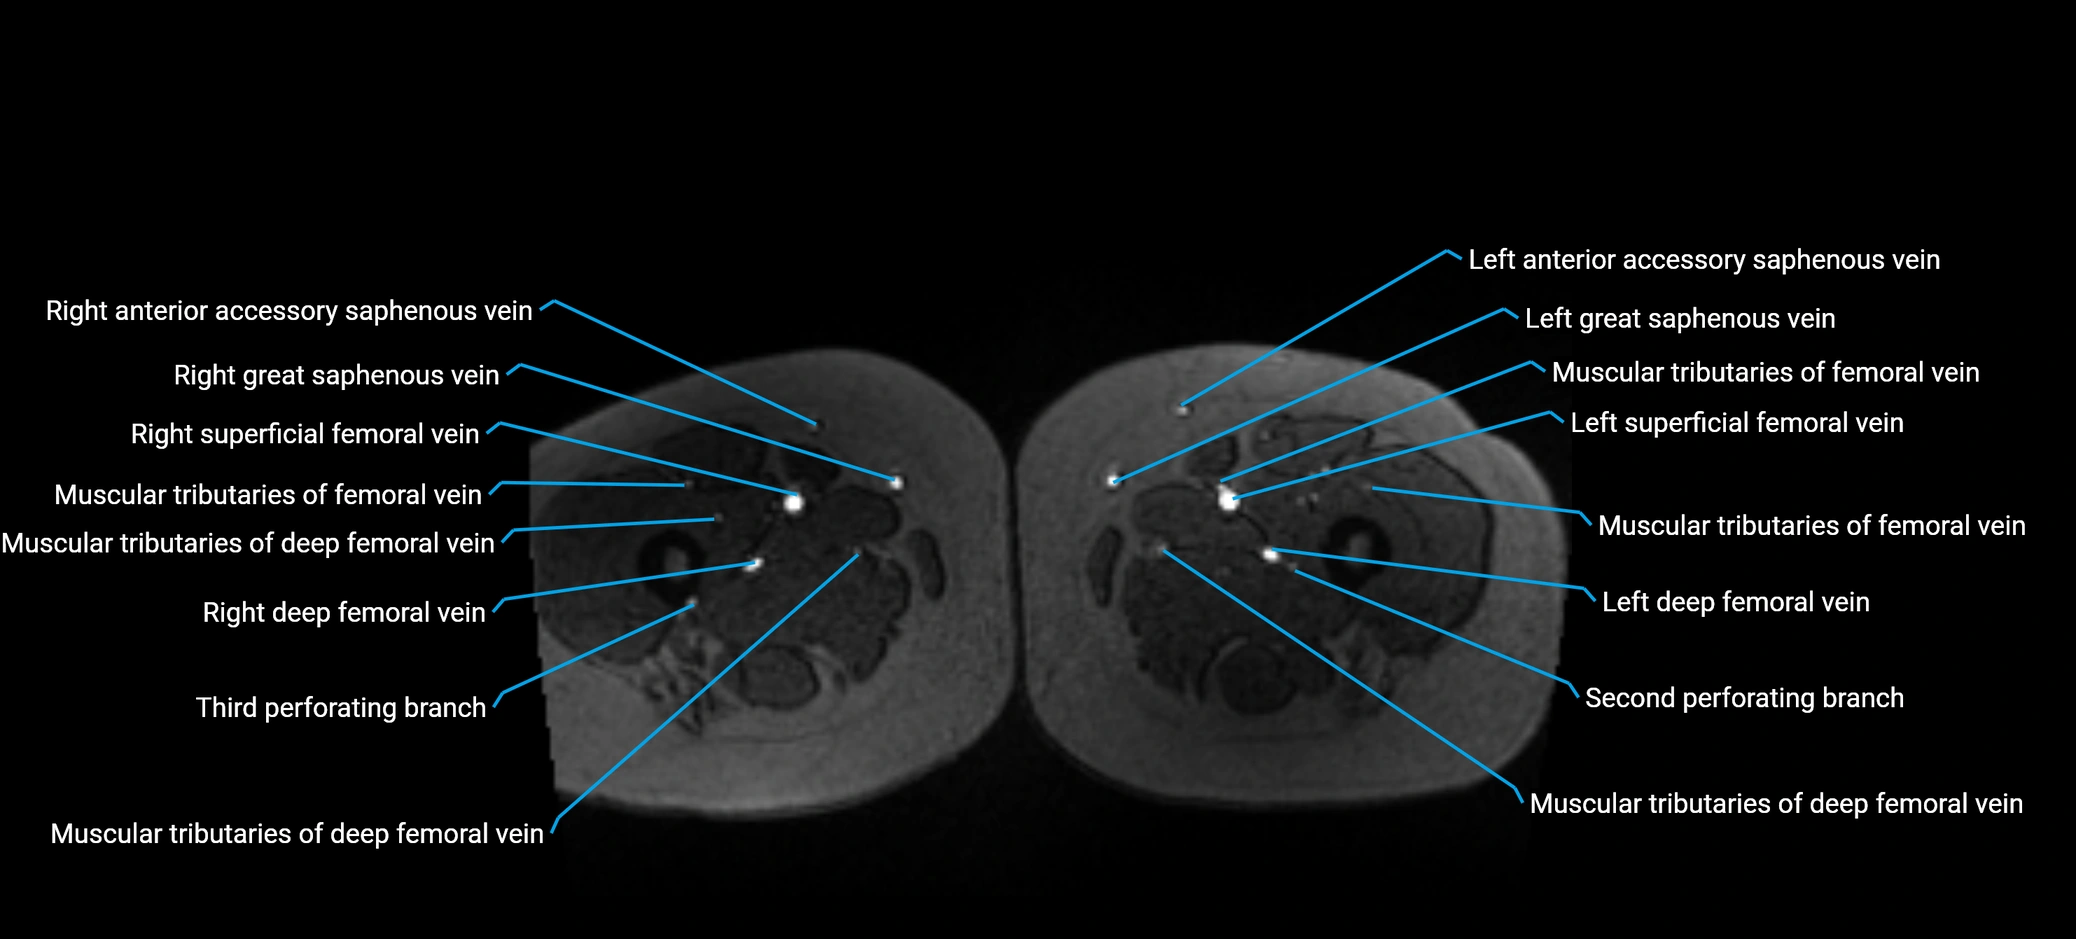

MRI image

image